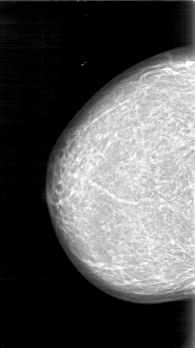

D_4026_1.LEFT_MLO

LEFT_MLO LINES 5386 PIXELS_PER_LINE 3181 BITS_PER_PIXEL 12 RESOLUTION 43.5 OVERLAY